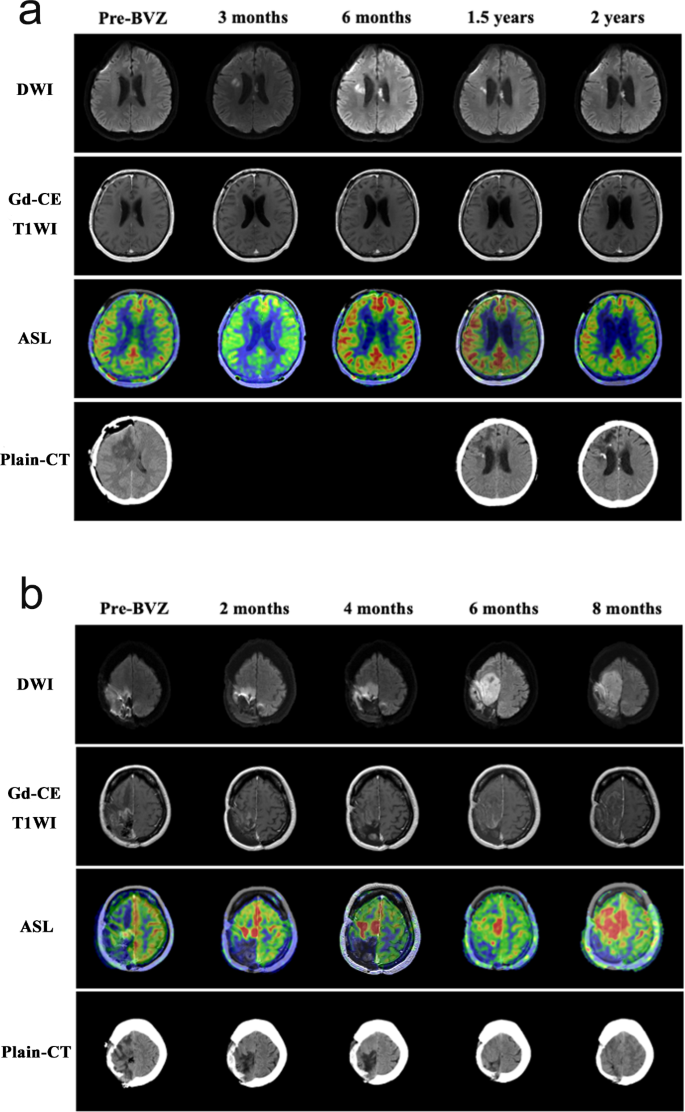

In 12 (70.6%) of 17 patients with calcification (Table 2), diffusion-restricted lesions coincided spatially with calcifications observed around the resection cavity or periventricular white matter (Fig. 3). These areas were always observed prior to the appearance of calcification, at a median of approximately 4.5 months after the initiation of BVZ treatment (Table 2). In all 12 patients, the size of diffusion-restricted lesions remained stable during a median duration of 5.5 (IQR, 2.3–19.0) months. On ASL imaging, diffusion-restricted lesions in all patients had hypoperfusion (Fig. 4a). Conversely, once diffusion-restricted lesions appeared in the non-calcification group, they gradually increased in size on DWI and had hyperperfusion on ASL imaging in all patients. These areas were ultimately diagnosed as recurrent lesions (Fig. 4b). We compared the ADC values of the two groups when diffusion-restricted lesions first appeared. The diffusion-restricted lesions in the calcification group had significantly lower ADC values than those in the non-calcification group (median, 0.56 × 10−3 mm2/s; IQR, 0.46–0.59 vs. median, 0.90 × 10−3 mm2/s; IQR, 0.84–0.99; p = 0.0031) based on the Mann–Whitney U test (Fig. 5).

Representative patients included a 39-year-old male with World Health Organization (WHO) grade 3 astrocytoma, in the calcification group (a, Patient 2 in Table 2) and a 39-year-old female with WHO grade 4 glioblastoma in the non-calcification group (b). Diffusion-weighted imaging; DWI (first row), gadolinium contrast-enhanced (Gd-CE) T1 weighted imaging (T1WI) (second row), arterial spin labeling (ASL) imaging (third row), and plain CT (fourth row) during the clinical course before and after bevacizumab (BVZ) therapy are shown. In the calcification group, diffusion-restricted lesions remained stable in size and had hypoperfusion on ASL imaging (a). Conversely, once diffusion-restricted lesions appeared in the non-calcification group, they gradually increased in size and had hyperperfusion on ASL imaging (b).

DWI is a form of MRI based on visualization of the random Brownian motion of water molecules in living tissue. In general, hypercellularity and necrosis restrict the diffusion of water molecules in the extracellular space, which results in a high signal on DWI and a low signal on ADC imaging in brain tumors, including gliomas23,24. In previous reports, the presence of BVZ-induced diffusion-restricted lesions in patients with HGG has been reported23,24,25,26,27,28,29,30,31, but there is no consensus about the mechanism and significance of this phenomenon. Some authors have demonstrated that BVZ-induced diffusion-restricted lesions predominantly represent necrosis, not aggressive hypercellularity, on the basis of pathological examination of biopsy specimens23,26,27,29. Mong et al. reported that the appearance of persistent diffusion-restricted lesions after BVZ administration is a favorable prognostic factor29. By contrast, some authors have reported that diffusion-restricted lesions reflect aggressive infiltrative tumor and result in worse OS30,31. In our study, diffusion-restricted lesions in the calcification group had significantly lower ADC values than those in the non-calcification group (Fig. 5), suggesting that measuring ADC values might enable us to identify patients with truly favorable prognosis. This finding is similar to those in previous reports where ADC values of diffusion-restricted lesions that were pathologically demonstrated as areas with necrosis were significantly lower than those of hypercellular lesions in patients with glioma treated with BVZ23,24. Nguyen et al. reported that the optimal ADC threshold for differentiating between hypercellularity and necrosis is 0.736 × 10−3 mm2/s.23These areas usually have low cerebral blood flow and cerebral blood volume on MR perfusion imaging, suggesting the utility of differentiating between necrosis and recurrent lesions26,27,29. Indeed, in the present study, all persistent diffusion-restricted lesions in the calcification group were associated with hypoperfusion on ASL (Fig. 4a). However, as shown in Fig. 4b, progressive diffusion-restricted lesions in the non-calcification group were associated with hyperperfusion, suggesting an increase in cell density due to tumor recurrence. In addition to the measurement of ADC values, hypoperfusion on MR perfusion imaging supports the hypothesis that diffusion-restricted lesions correspond to treatment-related necrosis, not tumor recurrence, in patients with HGG treated with BVZ. The radiological and histopathological findings in this study suggest that long-term BVZ treatment leads to the development of calcification within necrotic tissue via dystrophic calcification, which is consistent with the hypothesis that the development of persistent diffusion restriction is followed by calcification. If diffusion-restricted lesions appear around the resection cavity or periventricular zones after the initiation of BVZ treatment, it is necessary to check ADC values and perform MR perfusion imaging. Under these circumstances, we need to keep in mind that it is important to patiently continue BVZ treatment, considering the possibility of a favorable prognosis rather than interrupting treatment based on a misunderstanding of tumor recurrence.